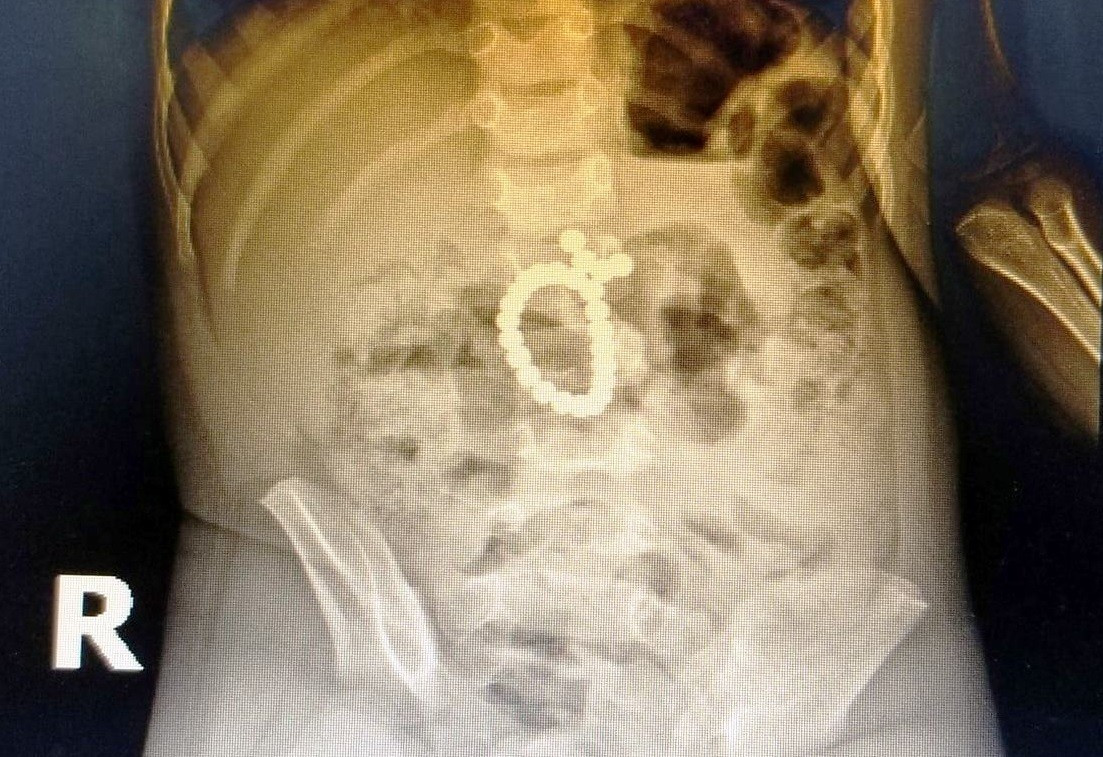

Tại khoa cấp cứu, trẻ biểu hiện đau bụng nhiều, quấy khóc, có dấu hiệu đề kháng thành bụng. Kết quả X-quang phát hiện dị vật nằm thành chuỗi trong ruột non, siêu âm ghi nhận viêm phúc mạc. Bệnh nhi lập tức được hội chẩn liên khoa và tiến hành phẫu thuật nội soi ổ bụng.

Ca mổ cho thấy ruột non bị thủng 8 lỗ, mỗi lỗ khoảng 2–3 mm, trải dài từ van hồi manh tràng lên trên khoảng 150 cm. Bác sĩ lấy ra 20 viên nam châm xếp thành 2 chuỗi, trong đó nhiều viên đã rỉ sét, gây tổn thương ruột nghiêm trọng. Các lỗ thủng được khâu vá thành công.

Các viên nam châm hít vào nhau xuyên qua thành ruột tạo thành nhiều lỗ thủng trong đường tiêu hóa của bệnh nhi